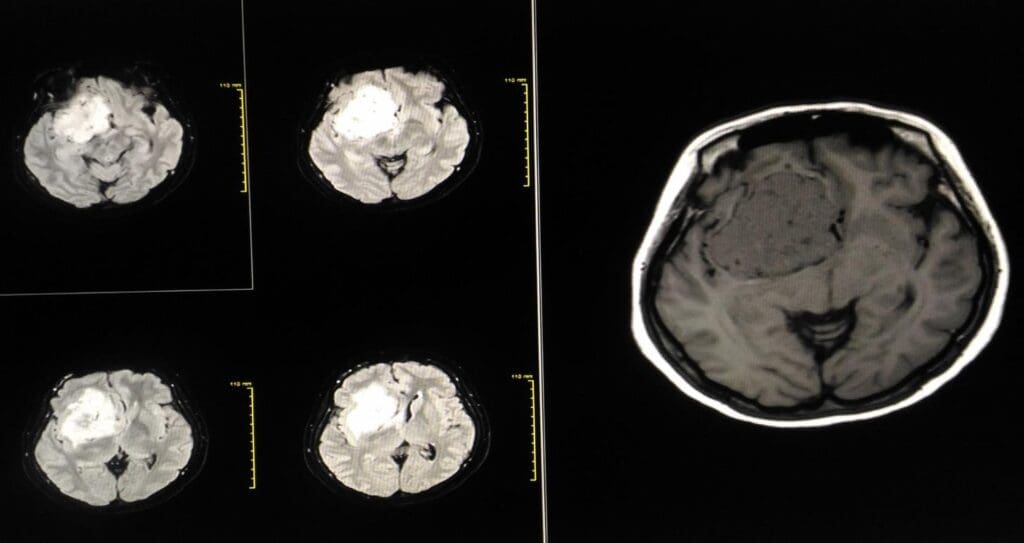

Advanced Imaging Techniques

Imaging is key in finding brain tumors. We use different methods to see the tumor clearly. The main ones are MRI, CT scans, and PET scans.

| MRI (Magnetic Resonance Imaging) | Uses magnetic fields to create detailed images of the brain | High resolution, excellent soft tissue differentiation |

Tumor Location and Accessibility Analysis

Then, we study the tumor’s location and how easy it is to reach. MRI and CT scans give us detailed info on the tumor’s size and position. This info is key for choosing the right surgery.